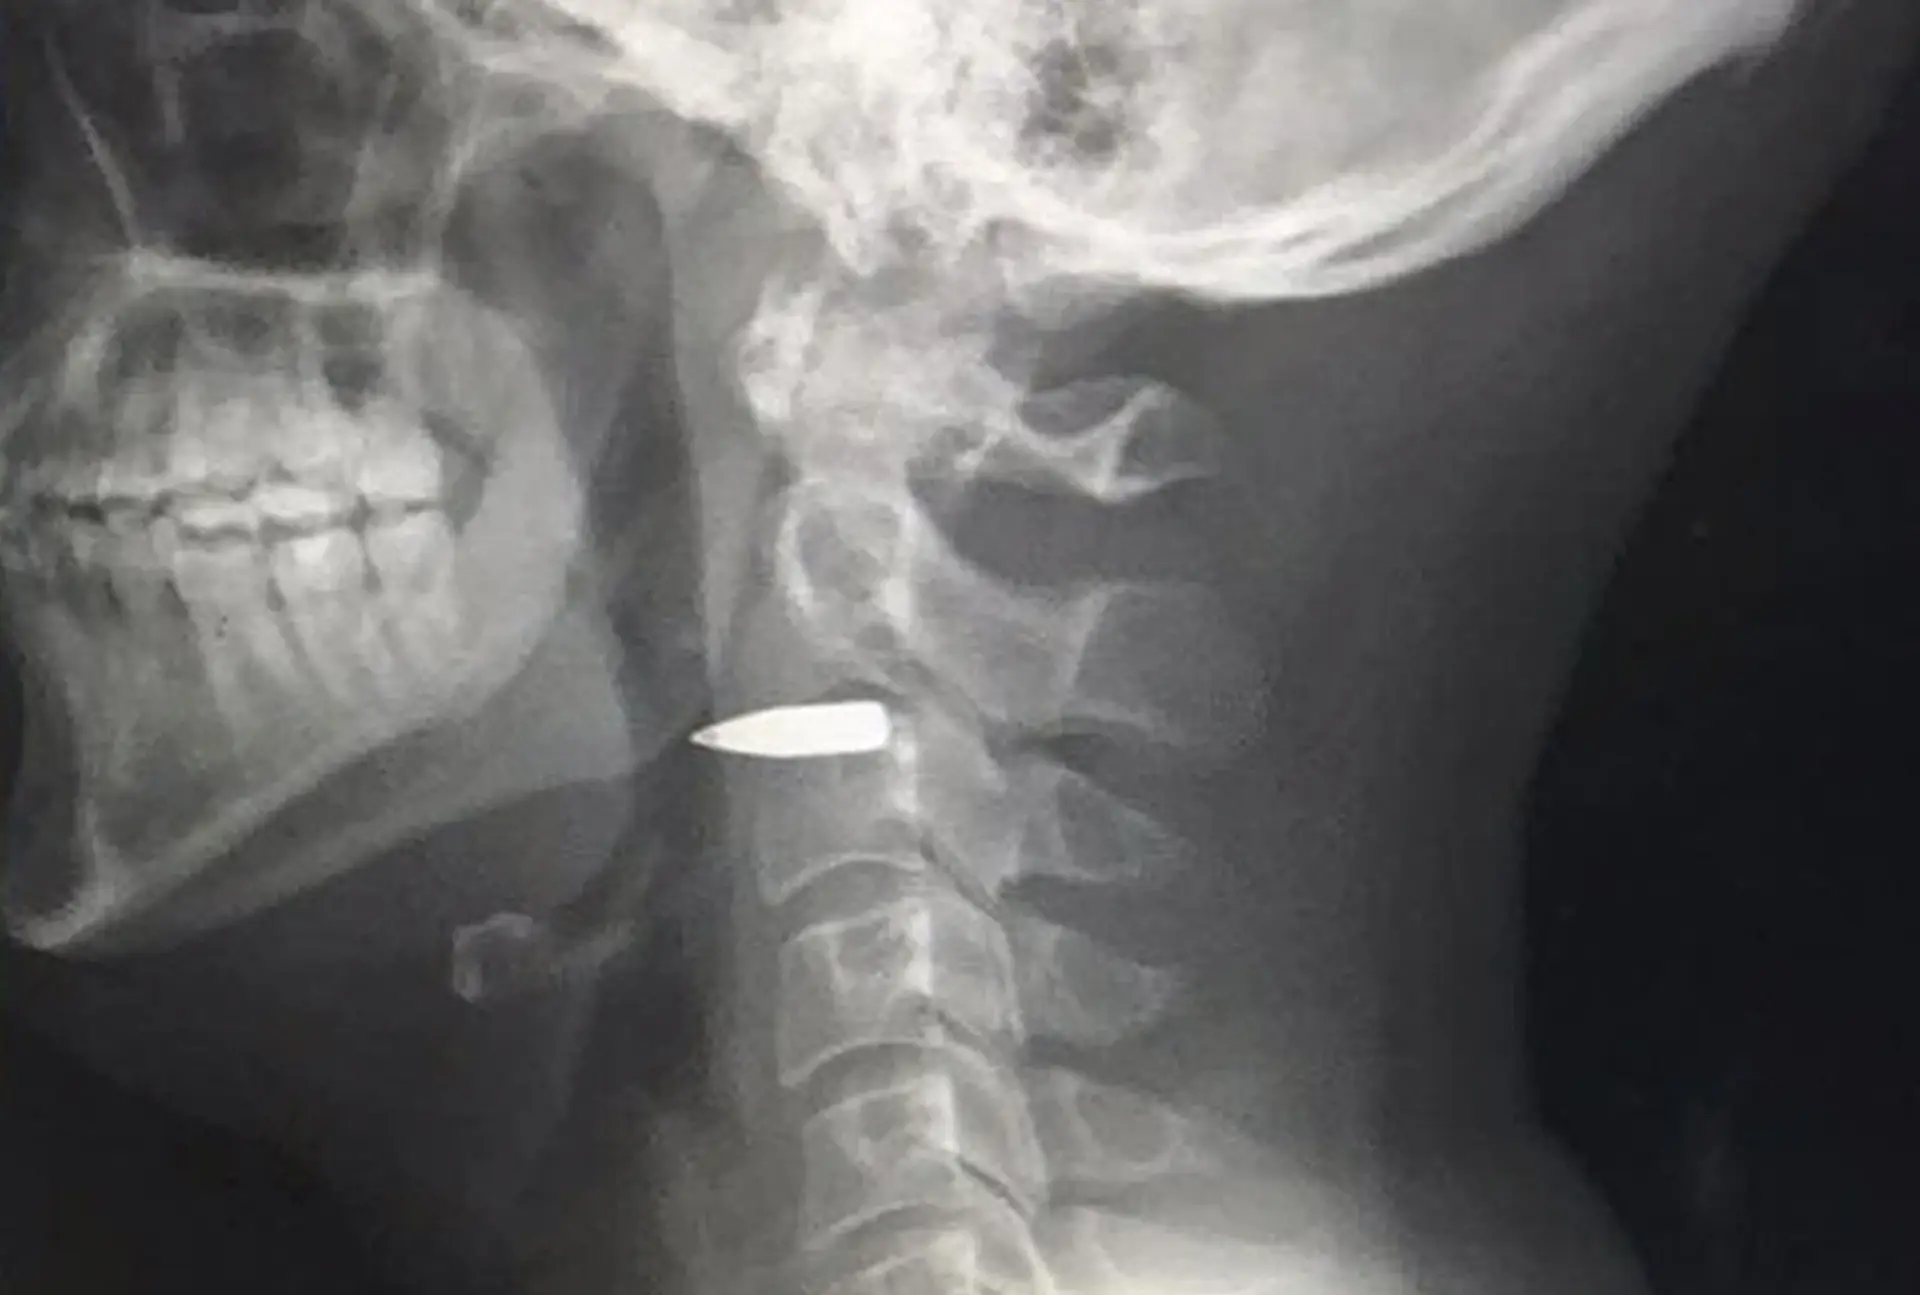

Adam Harvey publicou na rede social Twitter uma fotografia do raio-X, onde é possível ver a bala ainda alojada no pescoço.

Adam Harvey avançou recentemente no Twitter que tinha sido transferido para Manila, também nas Filipinas, para retirar a bala que continua alojada no pescoço.